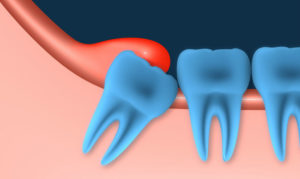

- Перикоронарит зуба мудрости (позадимолярный) развивается при длительном или неправильном прорезывании третьих моляров и связан с образованием десневого капюшона, его инфицированием и активным размножением бактерий. Причиной развития инфекции чаще всего становится нормальная микрофлора ротовой полости.

Данный процесс образуется долго, поскольку обычно развивается при частичном покрывании зуба десной, которая периодически травмируется зубами при смыкании челюсти, под нее попадают частички пищи, которые образуют микрофлору, благоприятную для размножения бактерий. Часто возникает при прорезывании зубов мудрости в нижнем ряду.

При перикороните, связанном с прорезыванием «восьмерок», очень часто встречается дистопия. Это аномалия, при которой зубы занимают неправильное положение в челюстной дуге (наклонены в стороны, вперед, назад) или же появляются за ее пределами. Дистопированные зубы прорезываются с трудом и, как правило, мешают прорезываться своим соседям.

Зубы мудрости из-за нехватки места располагаются в челюсти неправильно, что затрудняет их и без того непростое прорезывание. В результате длительного травмирования десна, которая покрывает непрорезавшийся зуб сверху, воспаляется. Иногда зуб мудрости прорезывается не полностью, над десной видны только 1-2 медиальных бугра. В этом случае также очень часто возникает перикоронит зуба.